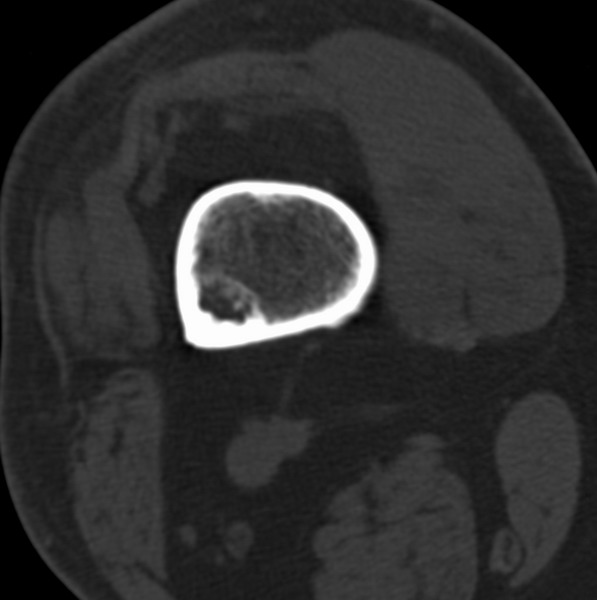

标题: CT21959:骨肿瘤请会诊。

右侧膝关节疼痛一月

男、48

股骨下段、胫骨上段。

1、股骨干骺端病变考虑干骺端纤维性皮质缺损愈后(非骨化性纤维瘤)改变,胫骨近端内生骨瘤(或干骺端纤维性皮质缺损愈后改变);

2、骨关节炎,骨质增生,股骨外侧髁退变性囊肿(关节面软骨下囊肿);

1、股骨干骺端病变考虑干骺端纤维性皮质缺损愈后(非骨化性纤维瘤)改变,胫骨近端内生骨瘤;